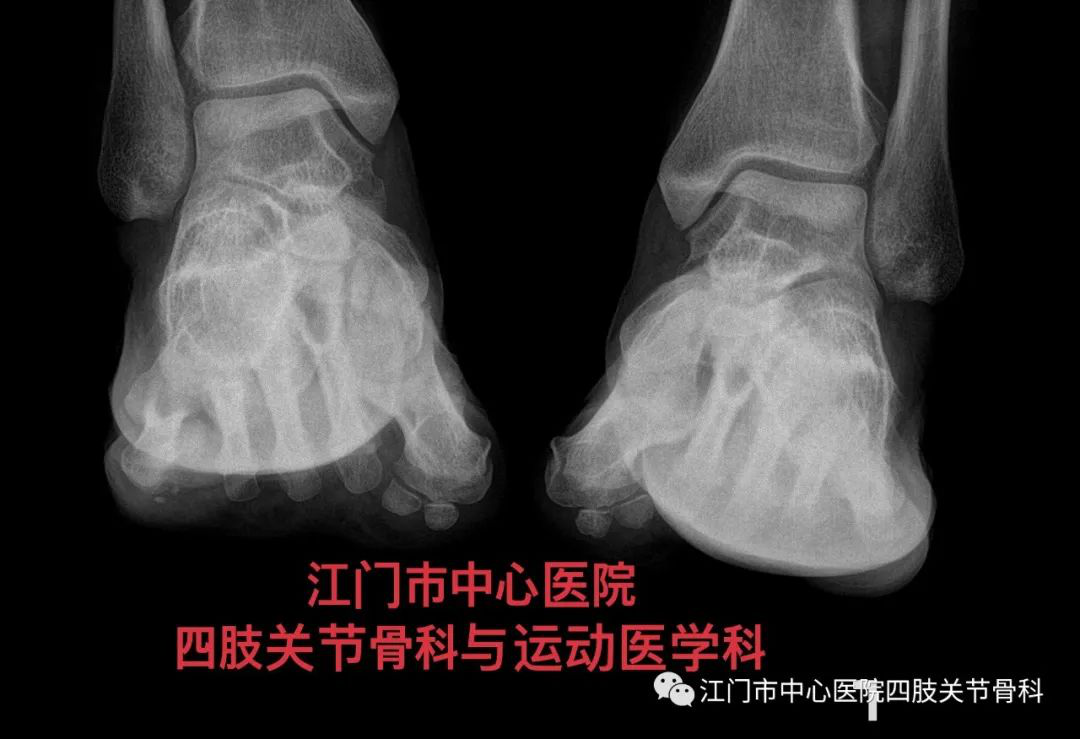

术前进行畸形角度的测量,制定确切的方案。

检查完善后明确了Mcbride+Scarf+Akin术